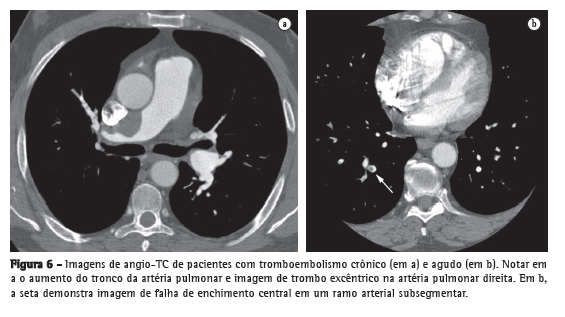

Bastante estudada, a angio-TC conquistou um amplo espaço na avaliação do TEP agudo, tornando-se um exame tão acurado quanto à angiografia pulmonar, mas desprovido do caráter invasivo. Uma série de estudos coloca a angio-TC como a primeira modalidade diagnóstica de imagem no estudo do TEP agudo.(34-36) O motivo está nas suas diversas vantagens: sua alta resolução permite a visualização de artérias e falhas de enchimento até a porção distal da vasculatura pulmonar, atingindo vasos subsegmentares de 2-3 mm (Figura 6); apresenta ótima concordância interobservador, bastante superior ao estudo cintilográfico; e sua sensibilidade é tão alta que um exame negativo pode indicar a suspensão de terapia anticoagulante com segurança.(37)

Deve-se ter cuidado, no entanto, com os perigos inerentes ao método. Fatores técnicos ou fisiopatológicos podem levar a interpretação de pseudofalhas de enchimento, trazendo resultados falso-positivos. Devem ser levados em consideração a possibilidade de artefato de movimento em pacientes taquipneicos, o intervalo de tempo entre a injeção do contraste e a aquisição da imagem e a ocorrência do fenômeno de vasoconstrição hipóxica em regiões mal aeradas. O aparecimento de tomógrafos de 64 canais abriu espaço para outro perigo: a possibilidade de excesso de resultados falso-positivos, que foi afastada em um estudo recente.(38)